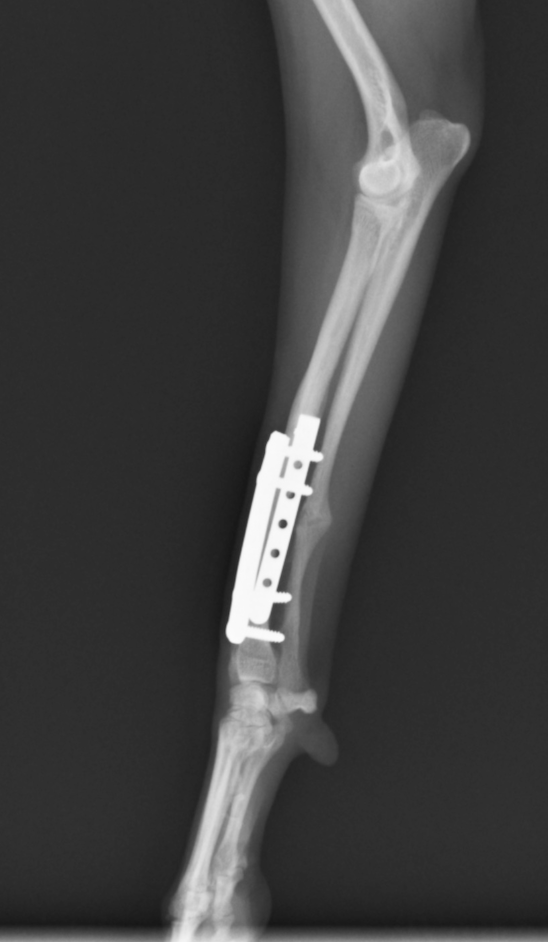

今回のワンちゃんも手術の決断をしてくださり、無事骨折した骨は、元通りのまっすぐな足の角度に治りました!

骨折の手術で大きな問題となるのは、癒合不全という、一見くっついているように見えるが、骨としての機能が損なわれてしまいずっと歩けないという状況です。不幸にも足を切らないといけないほどの状況まで行ってしまう子も中にはいるかもしれません。

当グループの骨折手術は初回手術(1回目の手術のこと)であれば100%治っております。他の病院で一度手術してから再手術の場合、すでに癒合不全が起こっていると当然手術は難しくなります。癒合不全の手術は1回で治らないこともあります。